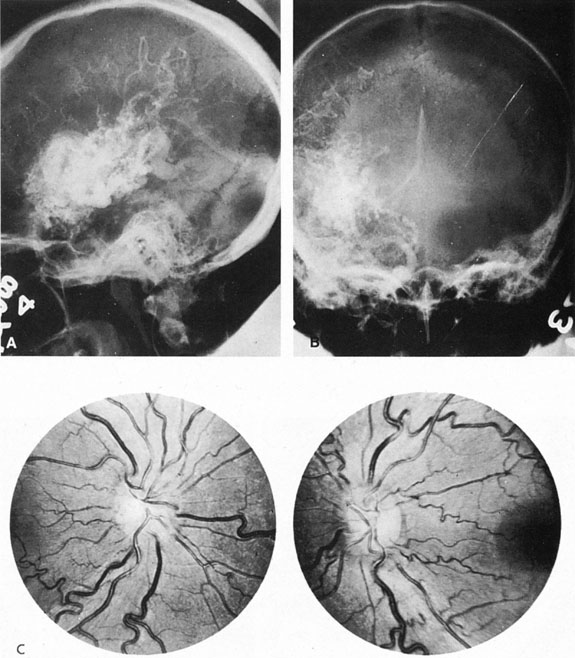

From 85% to 90% of AVMs are in the supratentorial compartment and are supplied primarily by the carotid circulation (Figs. 7 and 8). The remainder are supplied by the vertebrobasilar system. The approximate frequency of location is as follows: frontal, 22%; temporal, 18%; parietal, 27%; occipital, 5%; and deep intraventricular or paraventricular, 18%. The intracerebral site of the malformation does not necessarily indicate that there will be signs referable to that area simply from the mass effect of the malformation. Clinical features primarily result from subarachnoid hemorrhage or intraparenchymal hemorrhage with hematoma formation.

Fig. 7. Supratentorial arteriovenous malformation in a 28-year-old woman with a history of focal motor seizures for many years and a recent subarachnoid hemorrhage. A: Lateral projection carotid arteriogram demonstrating a huge deep hemispheral arteriovenous malformation. B: Frontal projection. C: Fundus photograph showing anomalous tortuous vasculature in each eye. No retinal arteriovenous shunt was detectable.